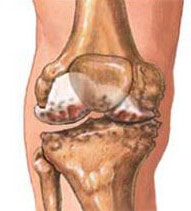

OSTEOARTHRITIS OF THE KNEE

Osteoarthritis (‘wear and tear’) of the knee is a common condition. It can affect the entire joint or just one compartment of the knee joint. Patients often experience pain which is related to activity, and find that rest relieves the pain.